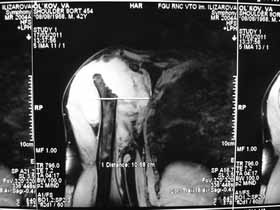

Re: Лизис костей плечевого сустава

Извиняюсь, что-то фотографии сразу не прошли. сейчас исправимся.